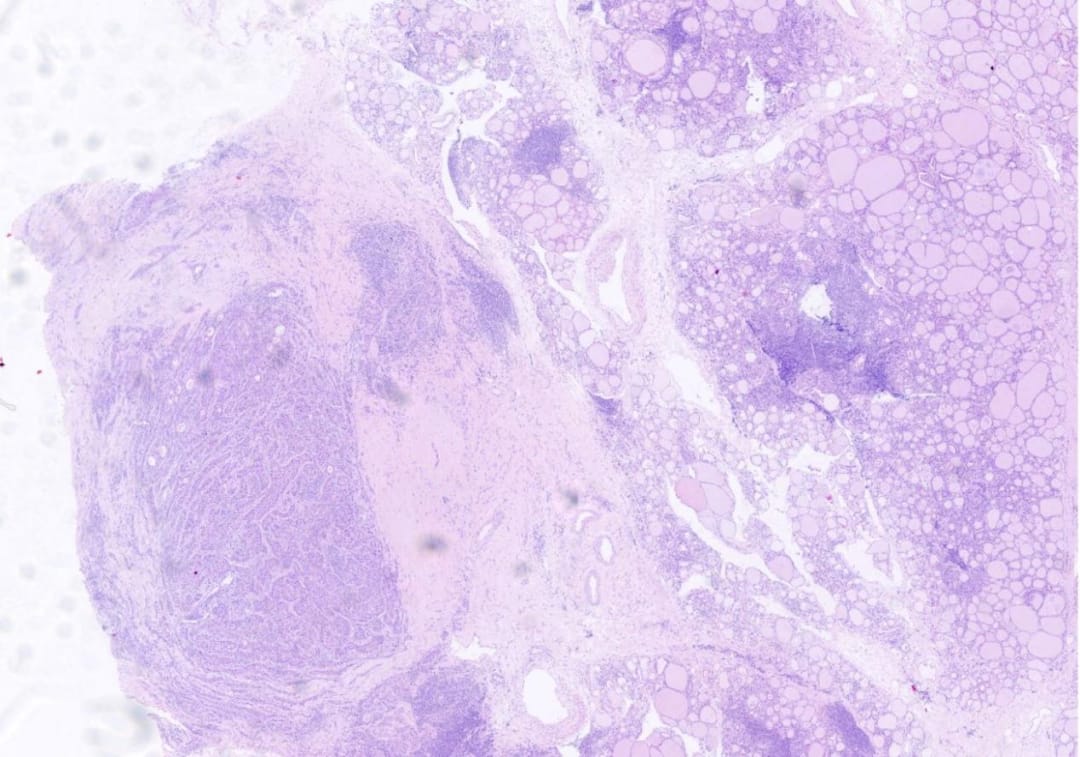

低倍镜,右侧为甲状腺组织伴淋巴细胞浸润,左侧为纤维间质内见肿瘤组织浸润性生长

肿瘤组织呈条索状、巢团状、实片状结构排列,间质淋巴细胞浸润

- 镜下所见: 显微镜下可见肿瘤组织呈条索状、巢团状、实片状排列于纤维间质中。肿瘤细胞胞浆丰富,嗜酸性,可见细胞间桥和核深染,核分裂象活跃。部分癌巢周边细胞呈栅栏状排列,局部中央形成角化珠。周围甲状腺组织伴有大量淋巴细胞浸润,呈桥本甲状腺炎改变。